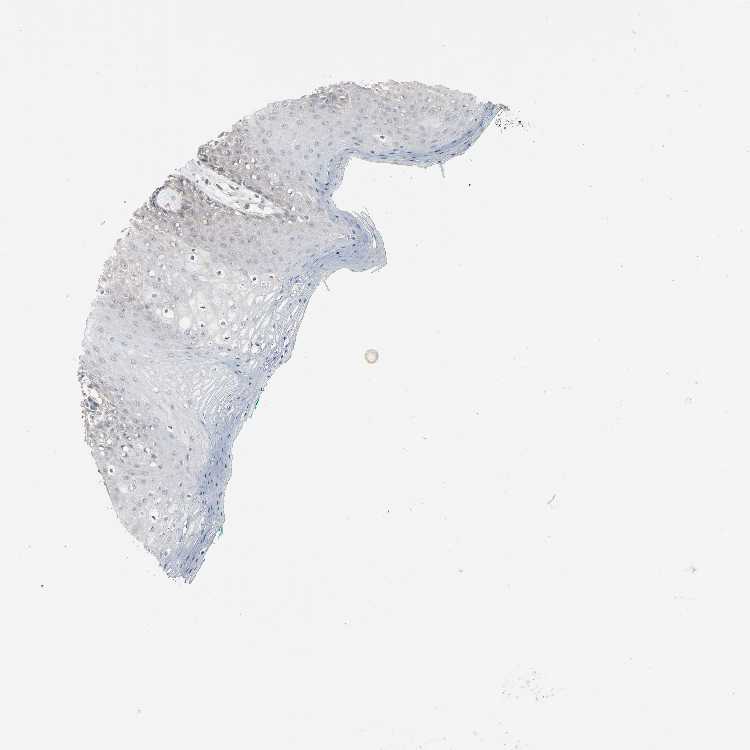

TISSUE PRIMARY DATA ORAL MUCOSA Show tissue menu

ORAL MUCOSA - Antibody stainingi

Antibody staining in the annotated cell types in the current human tissue is reported as not detected, low, medium, or high, based on conventional immunohistochemistry profiling in selected tissues. This score is based on the combination of the staining intensity and fraction of stained cells.

Each image is clickable and will lead to virtual microscopy that enables deeper exploration of all samples and also displays staining intensity scores, fraction scores and subcellular localization as well as patient and tissue information for each sample.

Antibody HPA004252Antibody HPA004472Antibody CAB000011Antibody CAB068180

Squamous epithelial cells LowNot detectedNot detectedNot detected